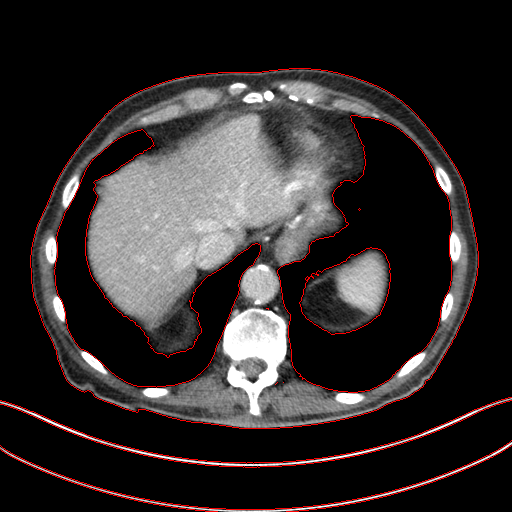

Figure 3: Comparison of denoising performance of different network. The boundary line of different organ extracted from the NDCT image is superimposed on other images. As seen, many pixels are missing around the boundary line in the output of M1

Refer to caption

(a) LDCT

(b) NDCT

(c) M1

(d) M2

(e) M3

Figure 4: Zoomed version of the ROI taken from the images of Figure 3. In the zoomed version missing boundary pixel is clearly visible in the output of M1.

This section systemically investigates the efficacy of every module proposed in this study. We considered three different networks; first, baseline model(M1), where the inverting block is replaced with dense block, and trained using minimizing mean square distance between two noisy observations(i.e. fsubscript𝑓\mathcal{L}_{f}). Next, two independent baseline model(one for forward mapping, one for reverse mapping) is jointly trained using a linear combination fsubscript𝑓\mathcal{L}_{f}, and rsubscript𝑟\mathcal{L}_{r}, similar to cycle consistent network paradigm. The forward mapping network is used for testing. We refer this model as M2. In both M1, and M2, we increased the depth of the network to make the representation power of these networks comparable with inverting network. Finally, the proposed method, referred as M3. Table 2 depicts the objective evaluation of the three networks using the D1 dataset. Both M2 and M3 use reverse mapping to regularize the network; the influence of the same in the denoising performance is evident from Table 2. Adding cycle consistency loss has improved the performance of the same baseline model significantly. The inverting network performed considerably better than the network M2. It improves PSNR by 0.23dB. As discussed in the above section, in case cycle consistency loss, an additional network is trained, but that does not always guarantee invertibility, whereas inverting network architecture inherently possesses reversibility, which acts as a strong regularizer. In Figure 3 we have shown denoising performance of different networks visually. To demonstrate the requirement of regularization, we first extract the boundary line of the various organ from the NDCT image and superimpose the boundary line on the output of different networks. As shown in Figure 3, many pixels around the boundary line of M1 network output are missing. Using the reverse mapping, the issue of the end-organ missing pixel is successfully overcome in M2 and M3. The granular pattern is also less present in the M3 than M2. The zoomed version of a ROI taken from the images of Figure 3 is given in Figure 4 for better perception. In Figure 5 we give an example of the performance of the invertible network in reverse mapping. Here, the predicted LDCT image is produced by using the predicted clean image of the forward mapping as the input for reverse mapping. As shown, the predicted noisy pattern is similar to the original noise pattern. The same streaking artifacts are present in both the noise pattern; also, the noise variance is different in the various spatial region depending on the signal intensity of the original CT image. It validates that the loss of information in reverse mapping is minimal. Due to the invertible network’s structural advantage, the network also preserves every information present in the input image in the forward mapping.